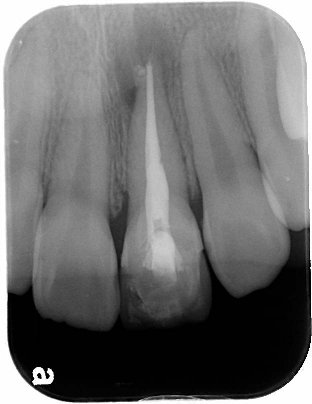

患者王小姐因左上正前牙疼痛劇烈前來求診 , 詳細問診之後, 了解該患者因多年前外傷造成前牙斷裂(見圖一) , 因當時只做緊急處理暫時用複合樹脂補起來 , 並未完整徹底根管治療 , 照數位X光(見圖二)後,發現左上正中門齒有根尖發炎的現象 , 初步診斷為慢性牙髓炎合併根尖骨質破壞 .

圖二 |

進行精密的顯微根管治療後 , 確認症狀消除 , 充填根管. (見圖三)

圖三 |